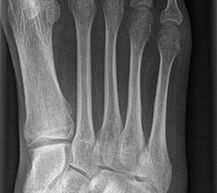

Die Standardröntgendiagnostik bei Fußfehlstellungen und asymmetrischen Arthrosen besteht in stehenden Aufnahmen des Fußes in 2 Ebenen (dorsoplantar und lateral), sowie einer stehenden ap Aufnahme des Sprunggelenks und eine „hindfoot alignment view“ nach Saltzman, mit der die inframalleoläre Rückfußachse beurteilt werden kann 7. Ganzbeinstandaufnahmen sind essentiell, um die mechanische Achse der gesamten unteren Extremität zu analysieren. Zur genauen Analyse des Knorpelzustands bietet sich die Kernspintomographie an. Für spezielle Indikationen steht das SPECT-CT zur Verfügung.